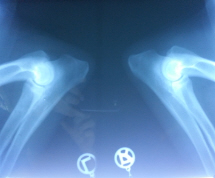

Hüfte, Ellbogen geröntgt, keine Auffälligkeiten